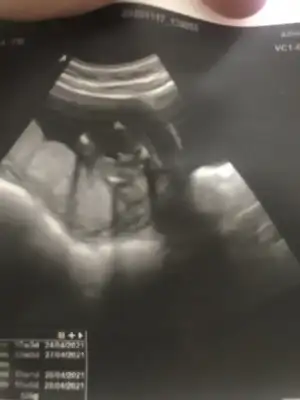

Kızlar merhaba benim doktorum 12 de kız gibi demişti kesin değildi tabi, bugün tekrar kontrol vardı 16+0 ım ultrason da 17 haftalık çıktı doktor bu sefer erkek dedi açıkçası çok güvenemedim. Altta resim yükledim bacak arası mı sizce çok anlamıyorum ultrasondan anlayanlar bakabilir mi acaba teşekkür ederim şimdiden 🙏

Bana bacak arası gibi geldi valla 😅 oğlun hayırlı olsun canım ❤️